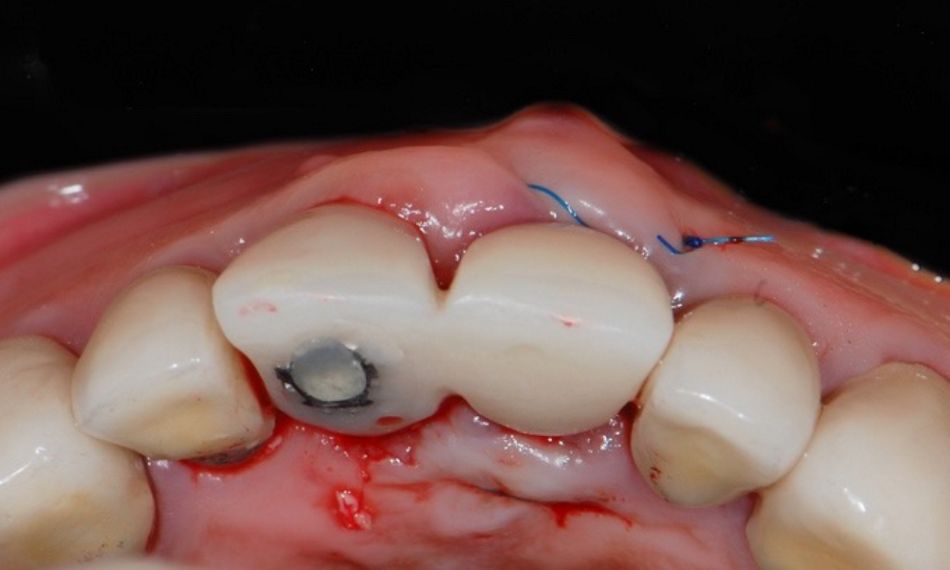

The patient came back four weeks after surgery for a follow-up visit. The soft tissue healing was uneventful (Figs. 23,24). Following our treatment plan, a guided Straumann® Bone Level Tapered (BLT) Implant Ø 3.3 mm, SLActive® 12 mm, Roxolid® was inserted at site #21, taking into consideration a minimal distance of 1.5 mm from the implant shoulder to the adjacent tooth at the bone level and a minimal distance of 3 mm between the implants (mesiodistal) (Figs. 25,26).